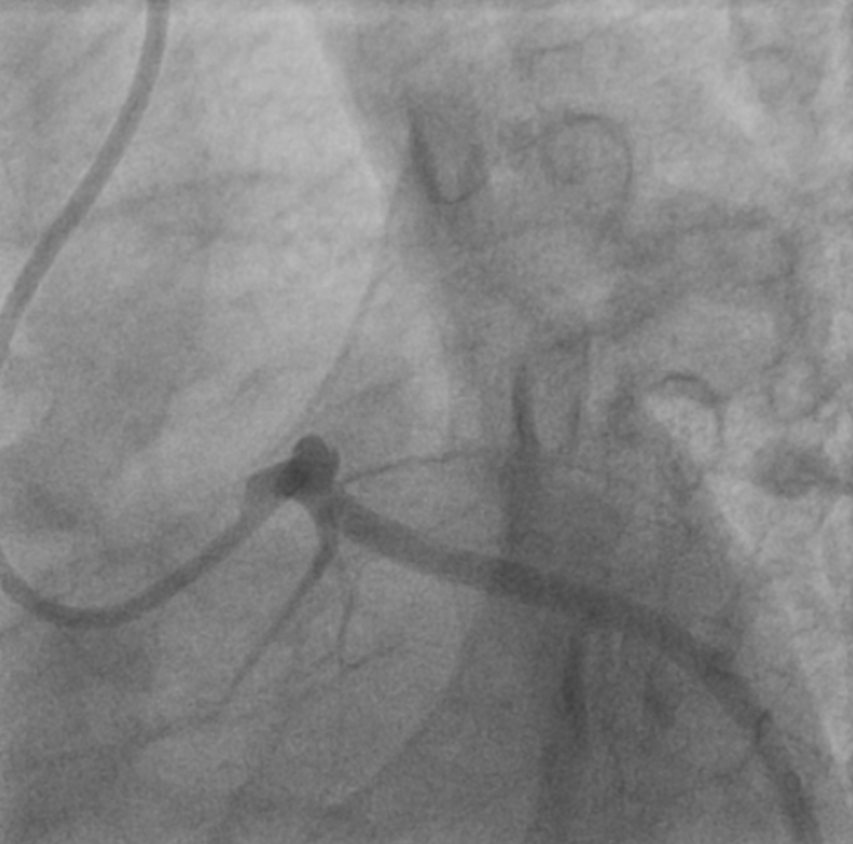

Relevant Catheterization Findings

Coronary angiography via rightradial access confirmed acute total occlusion of the proximal to mid LAD, whileLCx and RCA were patent. The lesion showed a thrombotic pattern consistent withplaque rupture likely triggered by blunt trauma. No evidence of coronarydissection or aortic injury was observed, confirming STEMI rather thanmyocarditis or myocardial contusion.